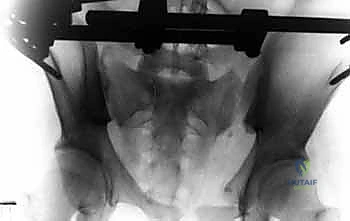

- الأشعة السينية (X-rays): يتم أخذ صور أمامية وخلفية (AP View) وصور بزوايا محددة (Inlet and Outlet views) لتقييم الإزاحة في حلقة الحوض.

- الأشعة المقطعية المحوسبة (CT Scan): وهي المعيار الذهبي. توفر صوراً ثلاثية الأبعاد (3D Reconstruction) تسمح للدكتور هطيف برؤية الكسر من جميع الزوايا، وتحديد مسار المسامير المعدنية بدقة متناهية قبل بدء الجراحة.

الخطوة الخامسة: الرد (Reduction) والتثبيت النهائي

يقوم الدكتور هطيف يدوياً بالضغط على الحوض لإغلاق "الكتاب المفتوح" (رد الكسر إلى وضعه الطبيعي التشريحي). بمجرد تحقيق الوضع الأمثل والتأكد منه عبر جهاز الأشعة، يتم إحكام ربط المشابك لتثبيت الإطار الخارجي بشكل صلب ونهائي، مما يمنع أي حركة إضافية للحوض ويوقف النزيف فوراً.